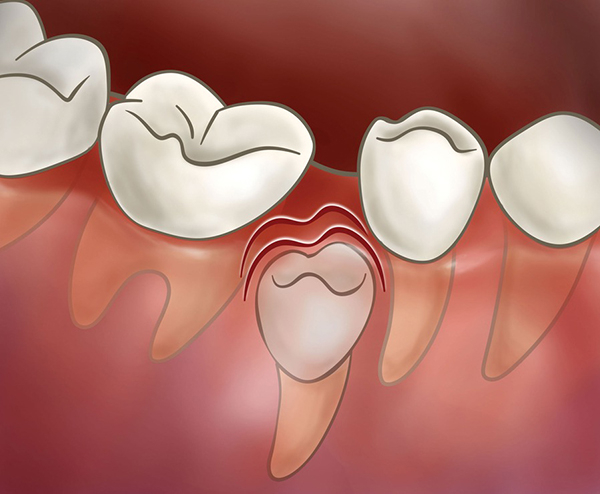

맹출 공간의 상실

충치나 치아 외상 등의 이유로 유치가 빨리 빠진 경우, 유치가 빨리 빠진 상태로 그냥 두게 되면 빈 공간으로 주변 치아들이 기울어져서 이후 영구치가 올라올 공간이 부족해질 수 있습니다. 이렇게 공간이 부족해지면 당연히 치아의 배열이 어긋나서 치아 교정을 해야 할 필요성이 커질 수 있습니다.

앞서 설명한 band & loop, distal shoe, nance holding arch, lingual arch 등의 공간유지장치로 빨리 빠진 유치의 공간을 보존해주지 못했을 경우, 영구치는 공간이 부족하여 매복된 상태로 있거나, 원래의 맹출 위치가 아닌 다른 위치로 삐뚤어져서 맹출하게 됩니다. 우리가 흔히 드라큘라 이빨이라고 하는 송곳니 덧니 역시 유견치(송곳니 유치)가 빨리 빠져서 송곳니가 나올 공간이 부족해졌을 경우 많이 발생하게 됩니다. 이러한 경우 송곳니가 내려올 수 있는 공간을 만들어주기 위한 교정이 필요하게 됩니다.